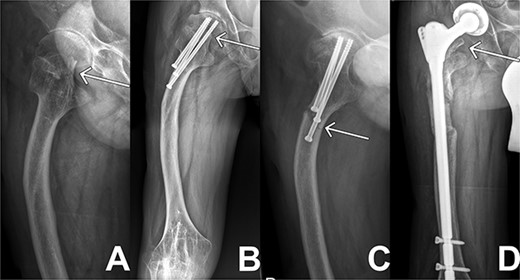

Initially, the patient presented to our joint consultation with a femur head necrosis ARCO 4, a femur deformity and arthritic hip changes, thus we initialized an elective total endoprosthesis (TEP) of the right hip. Before the operation, the patient was represented to our emergency department after a falling on the right hip with inner rotation pain. A medial femoral neck fracture of Garden 4 as seen in Fig. 1(A) was diagnosed. Because of his young age and the presented situation, we decided to perform a joint-presenting closed reduction and internal triple screw fixation of the proximal femur using 3 × 6.5 mm titanium cannulated screws the following day.

X-ray sequences of the right hip in different resolutions. (A) Representation of the medial femoral neck fracture before the first intervention as highlighted by arrow. (B) Osteosynthesis intervention of hip is highlighted by arrow few months after intervention. In addition, femoral deformity and knee rigidity are recognizable. (C) Periosteosynthetic fracture of the femoral shaft shortly before intervention. (D) Follow-up image of the inserted prosthesis material shows regular position.

The following week, the patient presented to the emergency department again with severe progressive wrist and ankle pain. Having diffuse myalgias and arthralgias with CRP values of 200 mg/l, we assumed the onset of JIA due to perioperative pausing of the Tofacitinib medication. His conditions improved after corticosteroid boost therapy with a dosage of 100 mg per day.

Two months later, the patient was represented to the emergency department after stumbling with progressive pain being conservatively treated due to bland diagnostics. Despite the good progress as seen in follow ups exampled in Fig. 1(B), the patient presented after another two months with atraumatic intense immobilizing pain of the right hip. Radiological diagnosis revealed a periosteosynthetic femoral shaft fracture as seen in Figs 1(C) and 2. The indication for the need of a TEP was given.

In the following days the patient’s pain and infection parameters increased. With the suspicion of infection, open joint lavage, debridement with drain and Vancomycin insertion was performed 2 weeks later. The intraoperative specimen didn’t reveal any microbiological findings. The clinical situation and infectious parameters developed worse. The CRP values progressively increased reaching its peak shortly after revision at 454 mg/l, the PCT values reached levels of 1.94 μg/l when measured over several days. After revision, appropriate antibiotic therapy and proper prosthesis inlay in radiological controls, an exacerbation of the JIA was now suspected because of hints like diffuse myalgia and arthralgia with further increasing CRP and PCT parameters. A prednisolone shock therapy was initiated. Under this therapy, pain and infection parameters decreased, thus confirming the assumption. The patient could be discharged to outpatient follow-up treatment. The following controls confirmed a good clinical course as seen in Fig. 1(D).